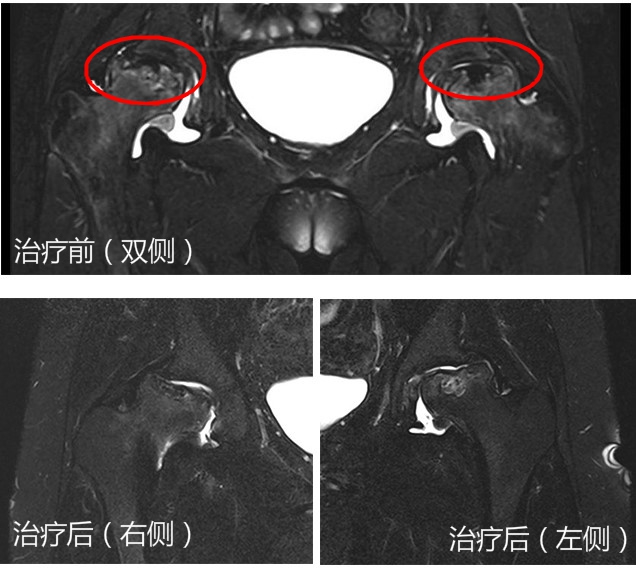

今年初,小茹来院复查了髋关节MR。经对比,双侧股骨头局部坏死病灶都有不同程度的缩小、局部有骨小梁的重构和股骨头坏死区的修复改变,关节腔内渗出明显减少。同时,疼痛评分已明显减轻至2/10分,可独立步行,步行距离较前明显改善,可如常上学。

治疗前MR检查显示,股骨头表面明显有破坏。经治疗后,修复了部分股骨头坏死病灶